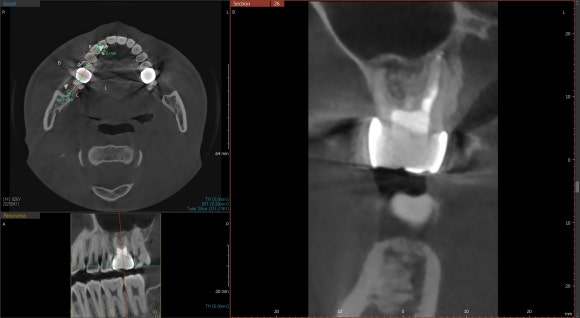

20240805

CT를 찍어보니 오른쪽 위 신경치료한 치아에서

염증이 발생한 것을 알 수 있었습니다.

치아 내부에 원인이 있는 경우,

염증은 대개 뿌리 끝에 동그랗게 잡히게 됩니다.

CT를 면밀히 분석한 결과,

이전에 받은 신경치료에서

놓친 부위가 있다는 것을

확인할 수 있었습니다.